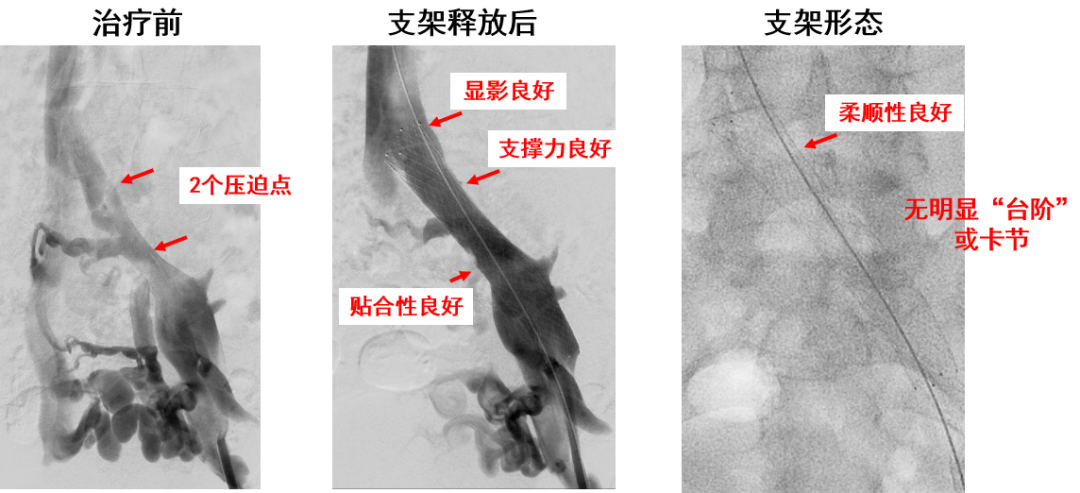

产品E:病例一(定位准确,柔顺性好)

产品E:病例二(多处受压)

优点:

近心端斜口,防对侧血栓形成

有较强的径向支撑力

柔顺性良好

显影性能较好,定位精准

锥形支架设计,贴合血管解剖结构和形态

缺点:

仅限用于髂总静脉,无延长段

近端径向支撑力略不足